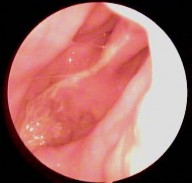

Hình ảnh nội soi tai

Ảnh 9 MN lõm, xanh MSBA. 1806217636 |